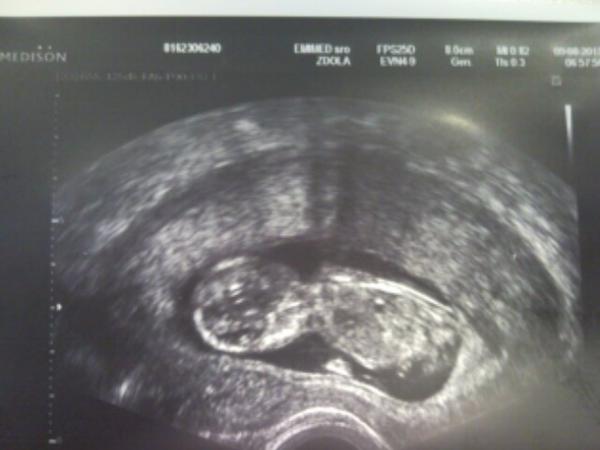

Babuleee, dnes som bola na prvom odbere krvy a robili mi aj sono a nasa mala vyhadzovala rucikami, nozickami, vystraja v brusku akoby ani nebolo 7.30 rano 🙂 vsetko je zatial v uplnom poriadku a my sa tesime, ze sme uplne v pohode. . . dokonca som videla ako otvara a zatvara pusinku, aj sme si to s doktorom zopakovali ten zaber, bolo to vtipnee 🙂 Taka malickost a aky krasny den mi spravila 🙂 . . baby drzim vam vsetky palce a nerobte vedu z tehotenstva. . . sme len tehotne, nie sme chore a ani niako vynimocne. . tak si nic neodopierajte, mne dokonca nebolo zakazane ani posilovanie z tazsimi vahami, pokial to nie je na brucho 🙂 a tuto je foto z dnesneho rana. . . 🙂